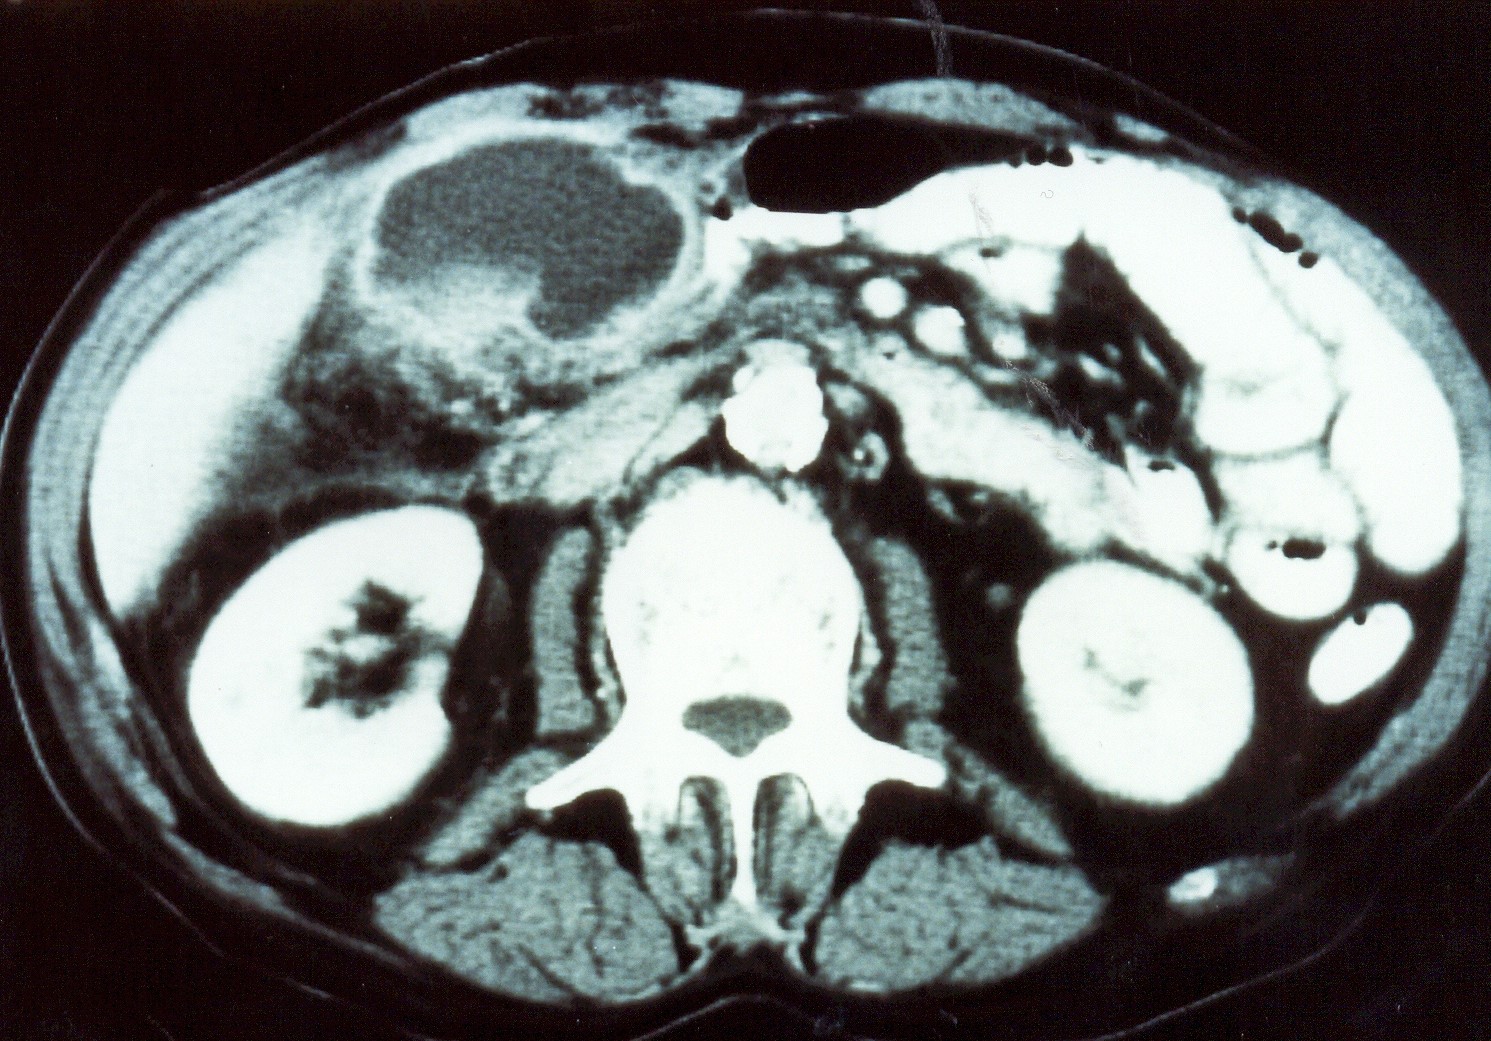

Abdominal CT scan. Red outline – Inflammatory fibroid polyp of the duodenum (Courtesy Dr. V. Penopoulos)